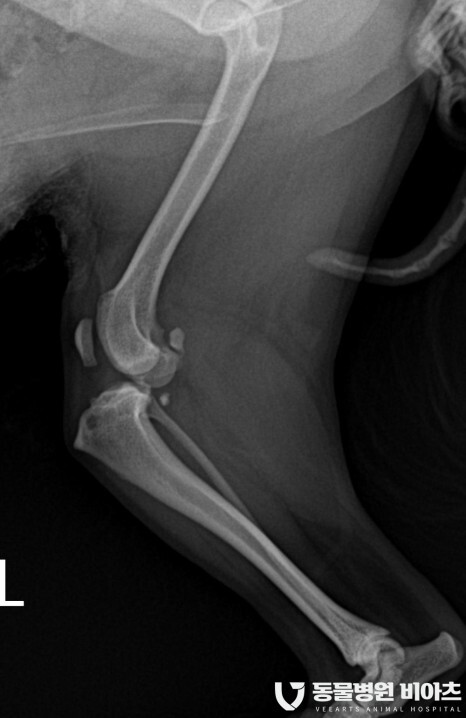

엑스레이 검사 결과

#전십자인대단열

#좌측 후지 슬개골 탈구 3기

#우측 후지 슬개골 탈구 2기

진단이 나왔습니다.